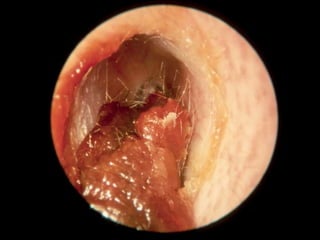

The Tympanic Cavity

CERUMEN CAST

OTOSCLEROSIS